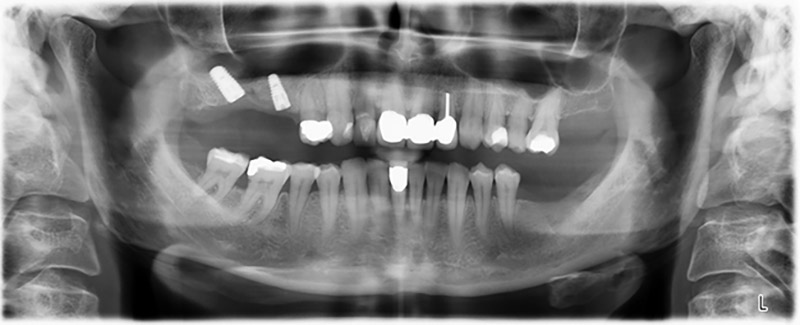

La paciente de 59 años presentaba una periodontitis avanzada, describía una desagradable sensación y un mal gusto proveniente del primer cuadrante. La evaluación clínica mostró en general marcadas profundidades de bolsa y una degeneración ósea muy avanzada en las regiones 16 y 14. El estudio radiológico corroboró estos resultados (figura 1). Las piezas dentales 16 y 14 no podían conservarse.

Unos seis meses después de la extracción de las piezas 16 y 14 se realizó una tomografía digital de volúmenes (DVT, Planmeca) para realizar una planificación adecuada y reducir los riesgos al mínimo. En este punto se constató que el hueso no se había regenerado en la cantidad deseada (figuras 2 a 7).